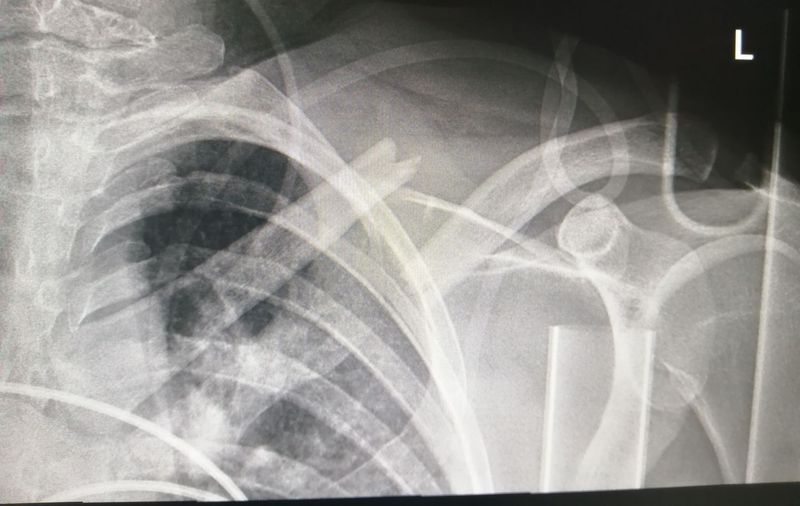

Clavicle AP View

Pain, reduced ability to move the affected arm

Xray

Left

Claviclefracture